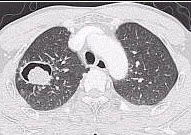

10、单项选择题

男性,45岁,有糖尿病史,突起寒战、高热,咳嗽,快脓性痰,伴胸痛2天,X线显示双肺实变,其中可见多个液气囊腔(如图),最可能的诊断是()

A.葡萄球菌肺炎

B.肺炎支原体肺炎

C.肺炎链球菌肺炎

D.肺炎衣原体肺炎

E.病毒性肺炎